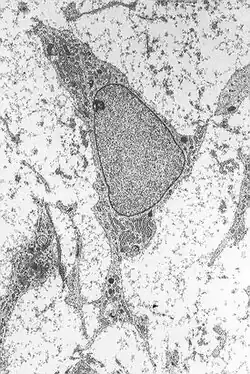

Mesenchymale Stammzelle

Mesenchymale Stammzellen (Mesenchymal stem cells, MSC) sind multipotente Vorläuferzellen verschiedener Zelltypen, die sich vom Mesenchym ableiten. Sie können sich unter anderem in Osteoblasten (Knochenzellen), Chondrozyten (Knorpelzellen), Myozyten (Muskelzellen) und Adipozyten (Fettzellen) differenzieren[1]. Außerdem konnte eine Differenzierung in Neurone, Astrozyten und Oligodendrozyten (Zellen des Nervensystems) beobachtet werden.[2]